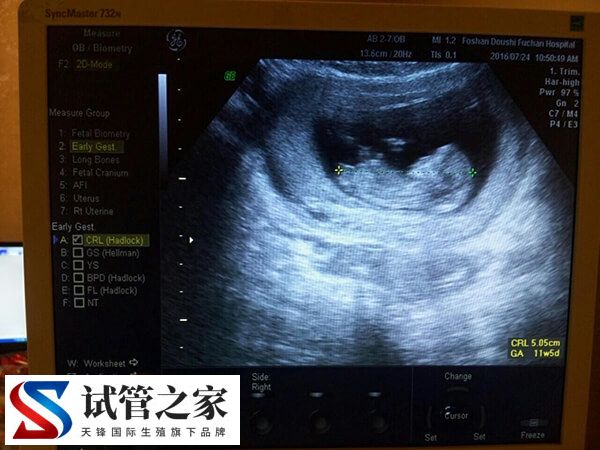

如果在接受辅助生殖技术(如试管婴儿)的促排卵治疗中,雌二醇主要由成熟卵泡分泌,若部分卵泡提前闭锁或发育停滞,即使激素水平达标,实际可用的成熟卵泡仍较少。

在试管婴儿促排卵过程中,大约5%-7%的患者可能出现卵泡内无卵母细胞的情况,导致激素水平与卵泡数量脱节,所以导致雌二醇600多取了3个卵泡的情况。